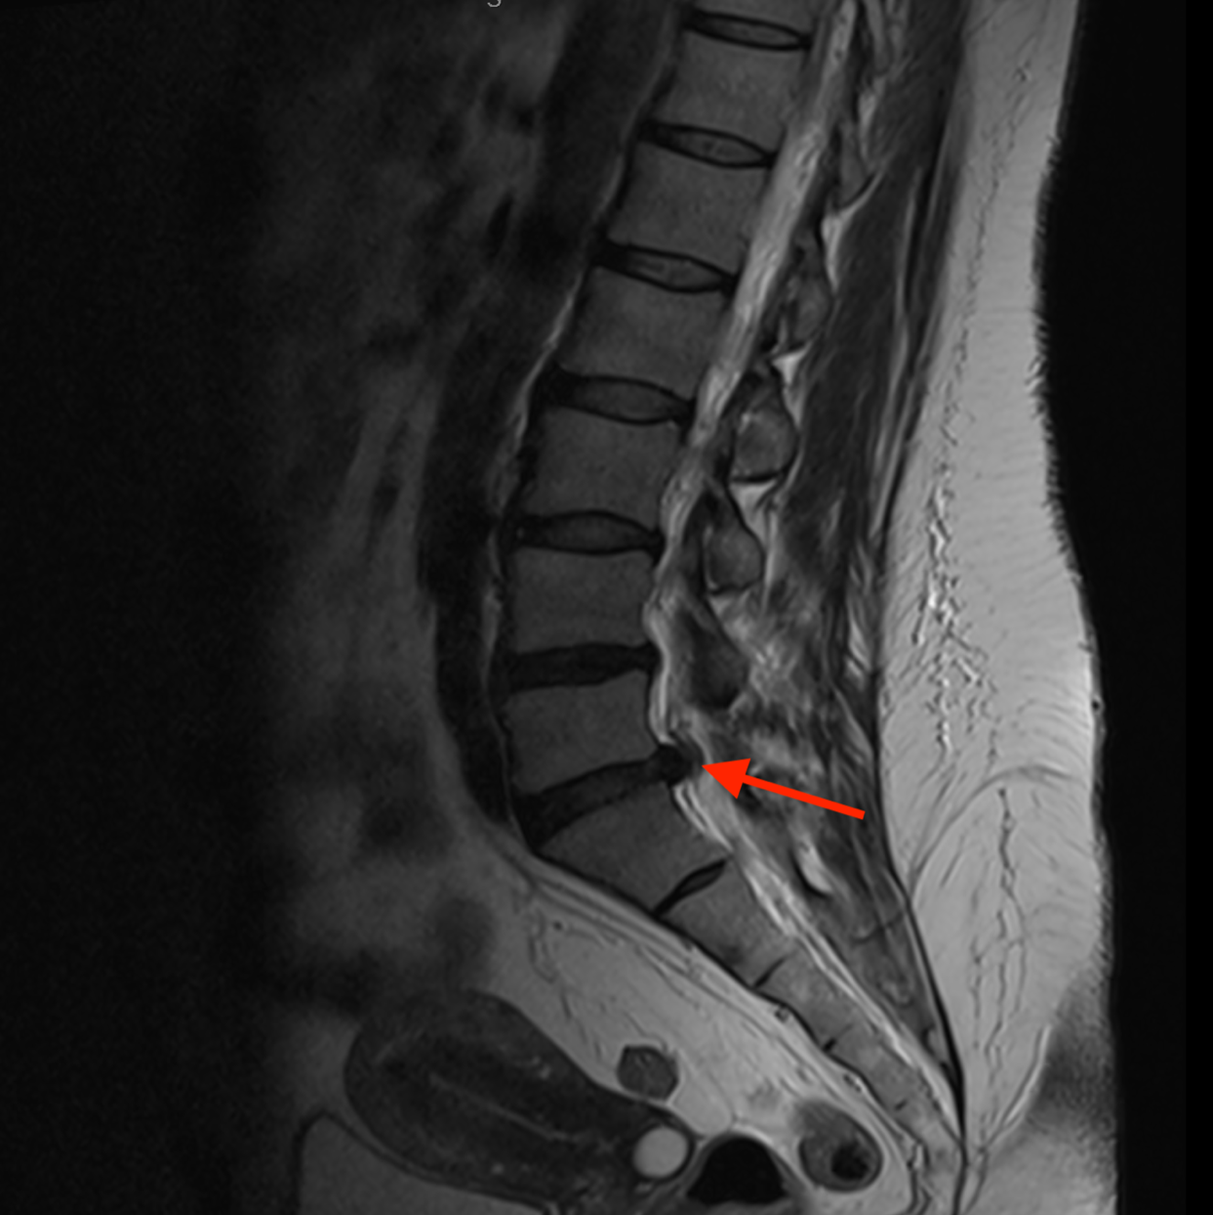

Dyskopatia -przyczyna dyskowa ucisku nerwu kulszowego

Nerw kulszowy może być podrażniony-uciśnięty przez przepuklinę krążka międzykręgowego. Rysunek 3.

Rezonans magnetyczny (MRI) – złoty standard w diagnostyce patologii układu nerwowego i narządu ruchu, pozwalający na dokładną ocenę dysków międzykręgowych, korzeni nerwowych i innych struktur miękkotkankowych.

Zdjęcie 4.

Wskazaniem do wykonania rezonansu jest brak efektów terapii opartej na odpoczynku, terapii manualnej oraz farmakologicznej, bądź też wystąpieniu objawów neurologicznych, ubytkowych (zaburzenia czucia, osłabienie siły mięśniowej, objawy nietrzymania moczu i kału). Jego wykonanie nie jest konieczne do rozpoznania dyskopatii ale jest konieczne w przypadku, gdy rozważamy leczenie operacyjne.